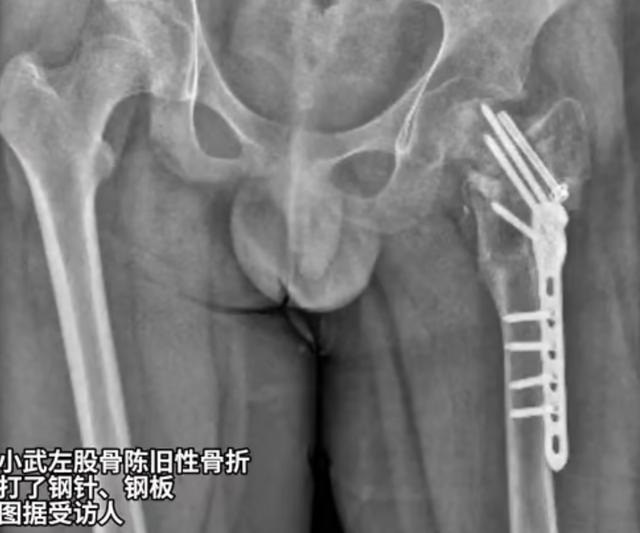

14岁双胞胎大武、小武于2023年6月21日、8月11日先后被送进福建泉州四维成长基地,小武在28天里遭到“通宵罚站、跪举long8官方入口水盆、扇耳光、关小long8官方入口黑屋、殴打”等虐待,致“左髋部重伤二级,胸部轻伤一级,双下肢轻微伤”,至今仍半残疾。